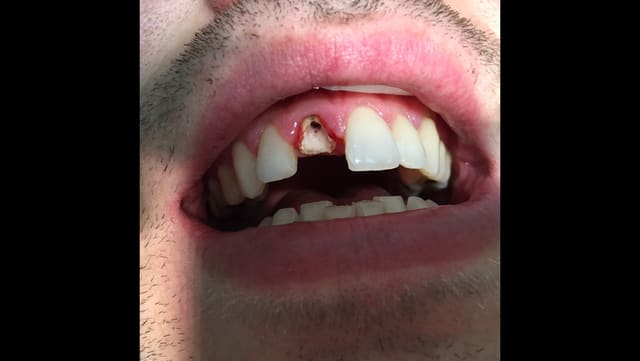

Patient vu au cabinet en urgence suite à descellement provisoire.

Celle ci comprenait un fragment de dent vestibulaire. Donc descellement dû à fracture.

Comme vous pouvez le voir contexte occlusal très défavorable avec la 42 en linguo-version.

c'est quoi le petit trait noir en vestibulaire? une fêlure?

pour ma part je vois une fracture:fêlure vestibulaire qui regle la question